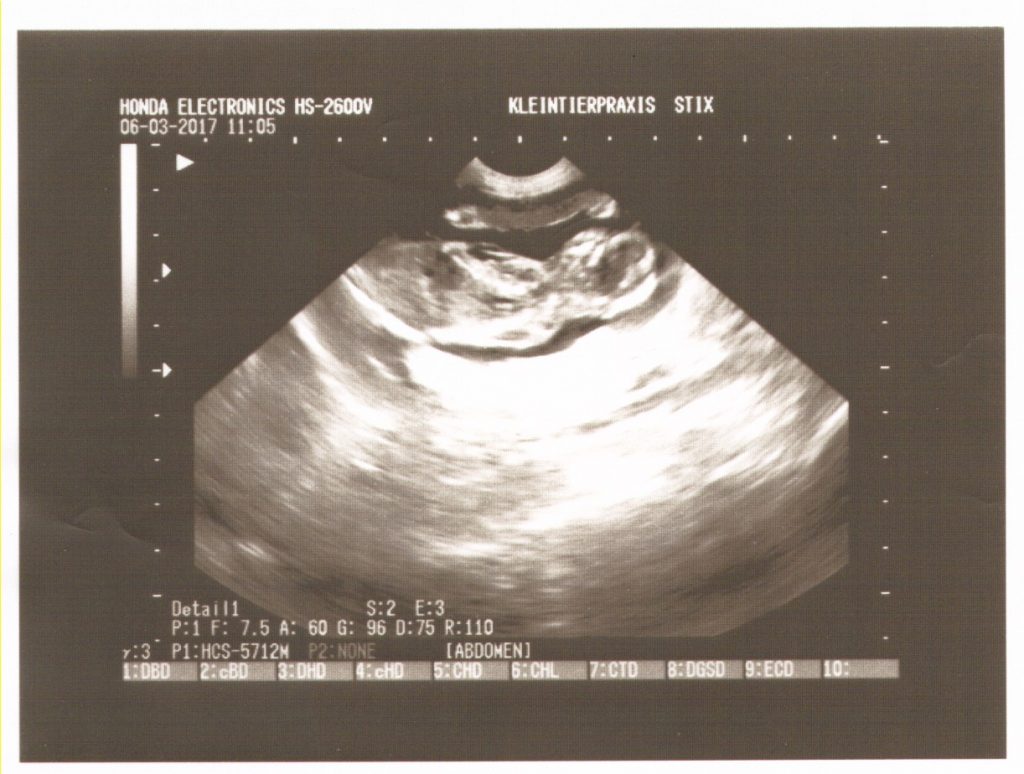

Wir waren beim TA zum Ultraschall und konnten mind. 4 Fruchtkammern mit Föten gut erkennen, sieht alles ok aus.

Ultraschall Beispielbild